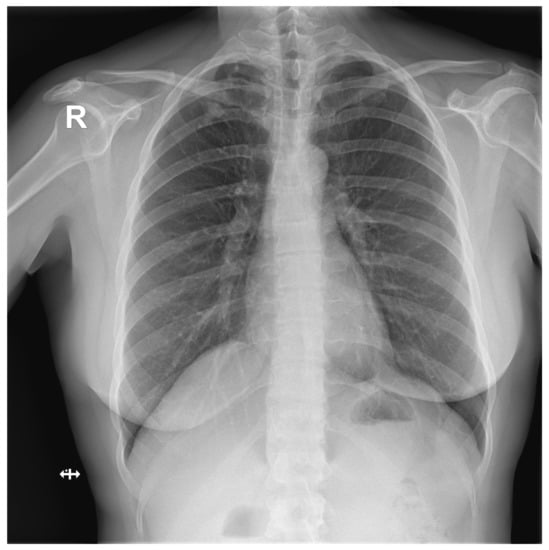

Figure A4.

False Negative image #3 incorrectly classified by DLAD software during the retrospective study. The software failed to detect a rib fracture. Assessed radiologists #5f0 and #630 also incorrectly classified this image as Normal. Assessed radiologist #442 classified the image correctly as Abnormal but failed to locate a rib fracture.